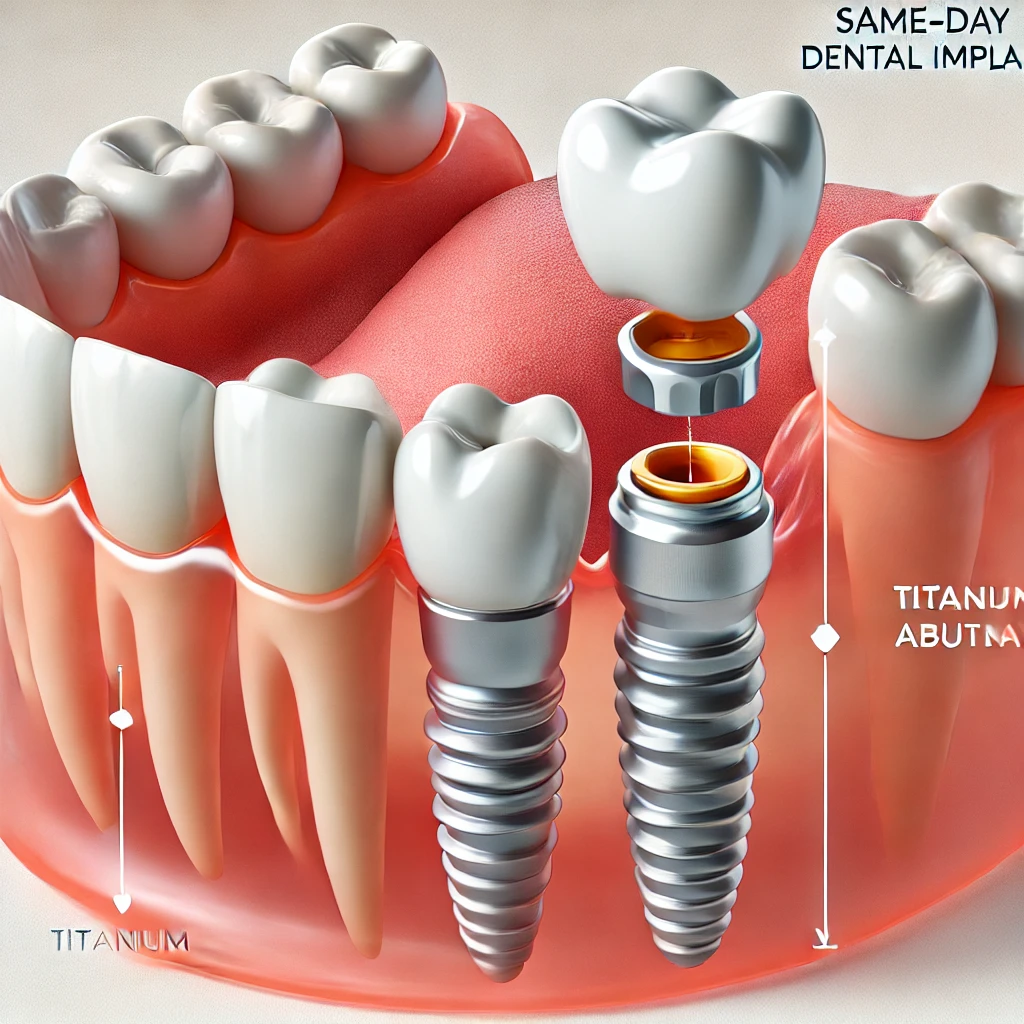

نغطي كل التخصصات الطبية

استیعاب کافة الحالات الطبیة لشمولیة التخصصات

أطباء الأسنان في تركيا

3 listings